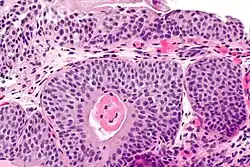

Micrograph showing cystitis cystica.